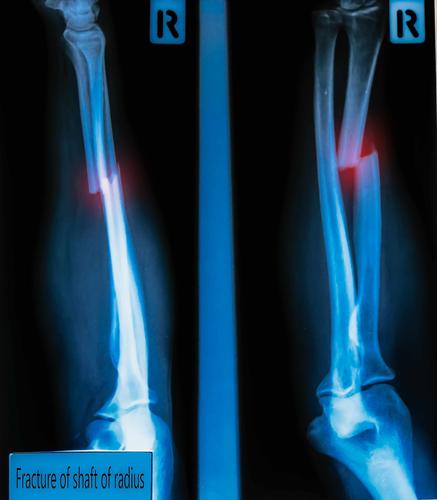

首先了解一下骨折,骨折的高发人群是老年人和儿童青少年,当然还有从事高危工作的成年人。通常来讲,骨折就是人体骨骼的完整性或连续性受到外力作用,并且超出骨骼的最大承受力,从而引起的骨骼裂隙、折损甚至断裂。可以使局部出现疼痛、肿胀,会使伤者行动受限,严重的还伴随休克症状。骨折的治疗相对简单,分为前期处理、石膏固定和后期康复三个阶段。